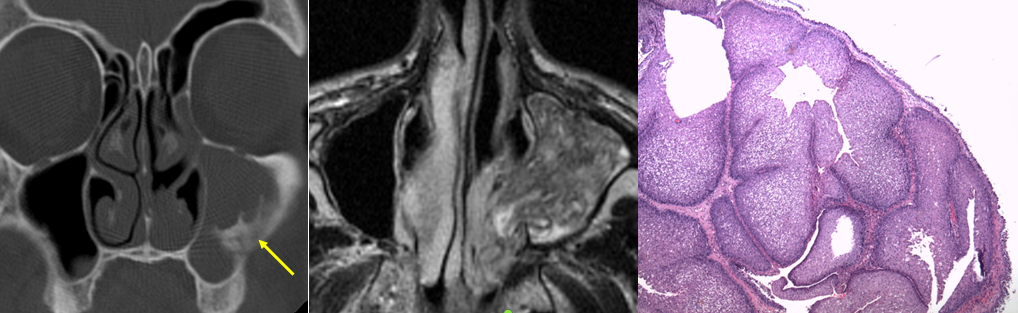

La TC (imagen coronal) muestra un tejido de partes blandas que ocupa el senomaxilar que se acompaña de un fragmento óseo en sumargen lateral (flecha). La RM (secuencia T2) muestraestriacionesestriacioneslineales (patrón cerebriforme) de la masa que ocupa totalmente el senomaxilarizquierdo y que se extiende a la fosa nasal. El estudio anatomopatológico identifica una proliferación celular de patrón endofítico, constituido por células poligonales de núcleo claro.